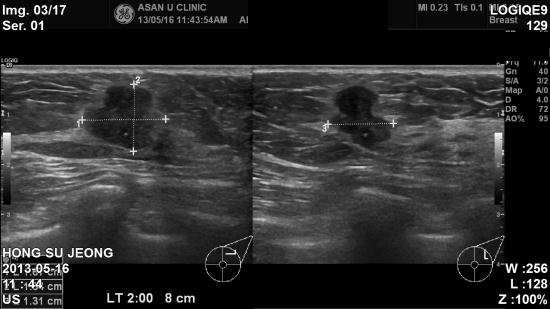

8cm 떨어진곳에서 석회화 소견 있어